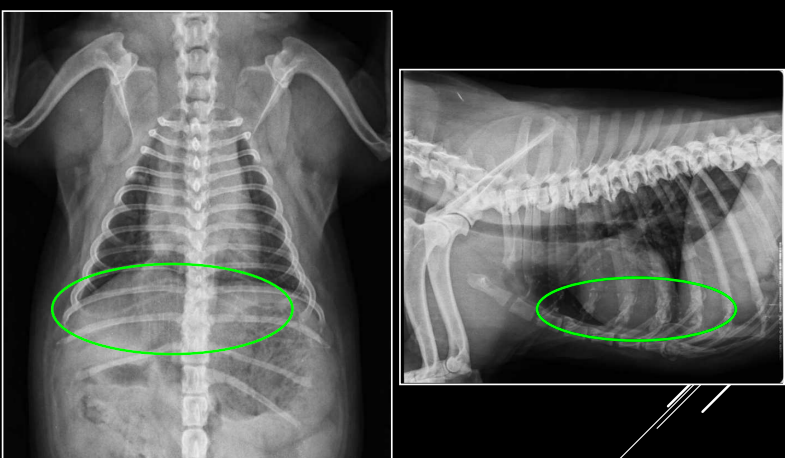

Por consolidación: edema, neumonía, hemorragia, neoplasia.

Por atelectasia: obstrucción, compresión, neumotórax, efusión pleural.